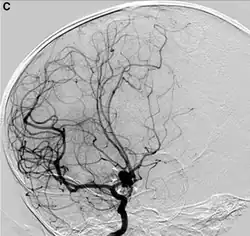

- Tętnica szyjna wspólna - zaburzenia widzenia, omdlenie, TIA, bolesność w przebiegu naczynia (carotydynia), udar mózgu

- niedokrwienny udar mózgu